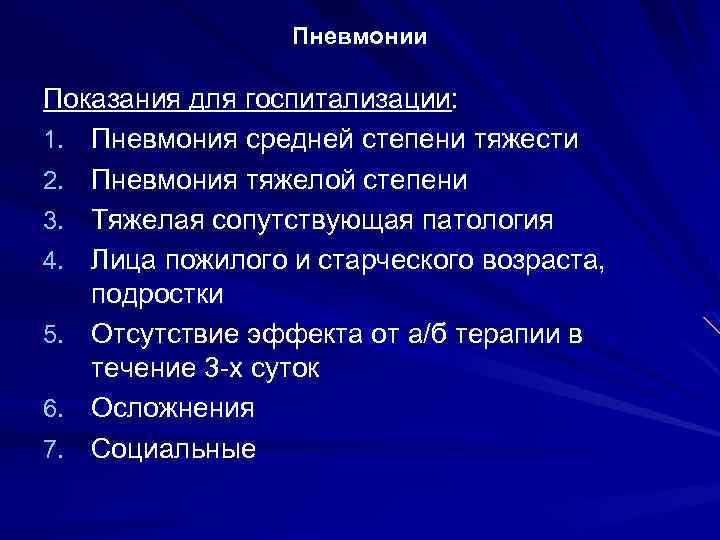

Острая внебольничная пневмония по МКБ-10: признаки и примеры